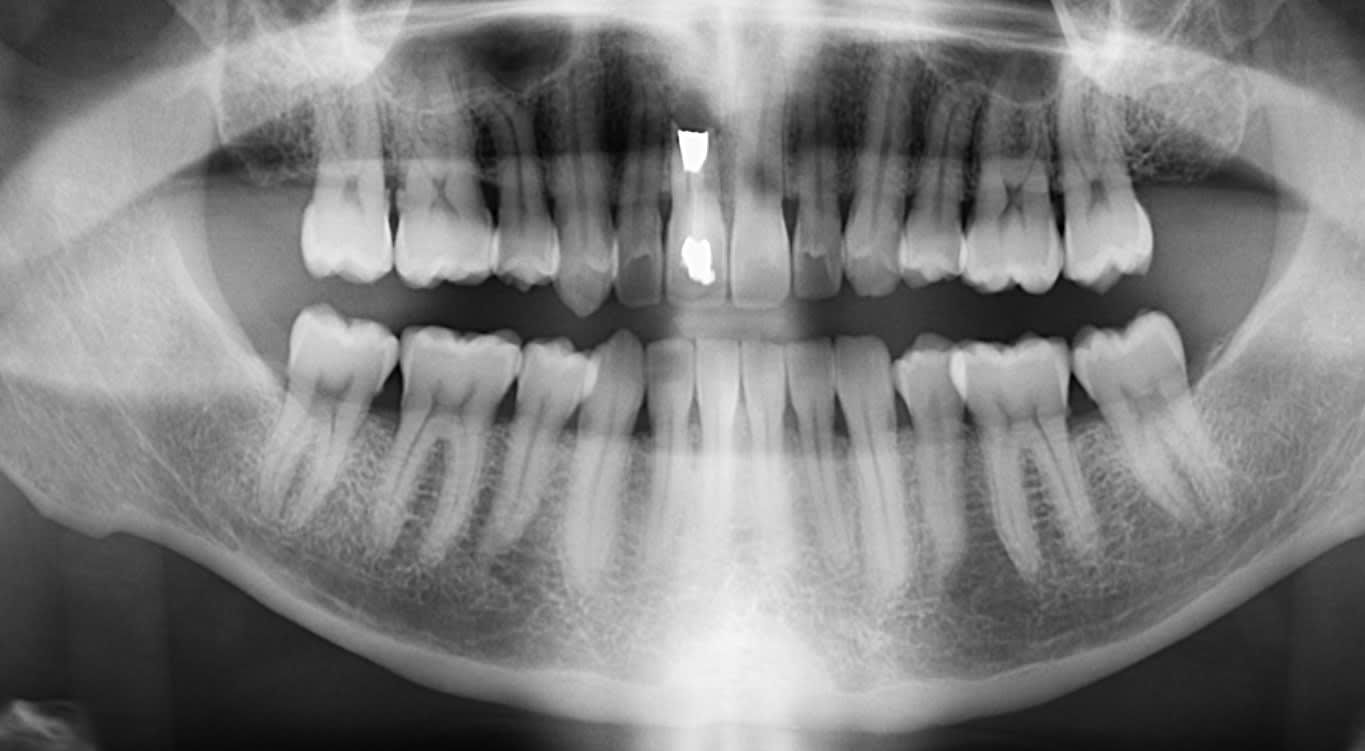

chers confrères, votre avis sur ce patient 47 a ; 11 dévitalisée en 1981 suite trauma , puis resection apicale en 1983 professeur cavaillon a versailles ( enfant 12 a)

image constante radio claire depuis 1983 inchangée en région apicale sans aucun signe clinique.

épisode douloureux il y a 15 ans, une stomato a simplement rouvert le canal , nettoyage et comblement ( partie en retraite pas d infos supplémentaires) guérison immédiate sans abord apex.

dent non douloureuse depuis 15 ans

depuis quelques mois : douleurs uniquement a la mobilisation de la dent , pas de gonflement apical ni fistule , ni à la pression au dessus 11

votre avis ; reprise simple traitement canalaire possible comme il y a 15 ans? possible action sur le kyste ? possible greffe osseuse le cas echeant?

vous remerciant pour vos avis conf. ci joint pano 2014 asympto pano 2018 dent 11 2018 et scan 2018

on peut noter sur les panos comment la necrose a evolue au meme rythme que la parodontite entre 2014 et 2018

la meme quantite de perte osseuse

Moi je laisserai comme ça si pas de symptômes douloureux pour le moment puis exo et comblement osseux en perop, attends 6 mois avec un provi collé et implant

bjr comblement osseux donc greffe au moment extraction. vous laissez pas cicatriser avant greffe? pensez vous qu il y ait infection et necrose evolutive ou bien stationnaire d apres scann et pano ? conf